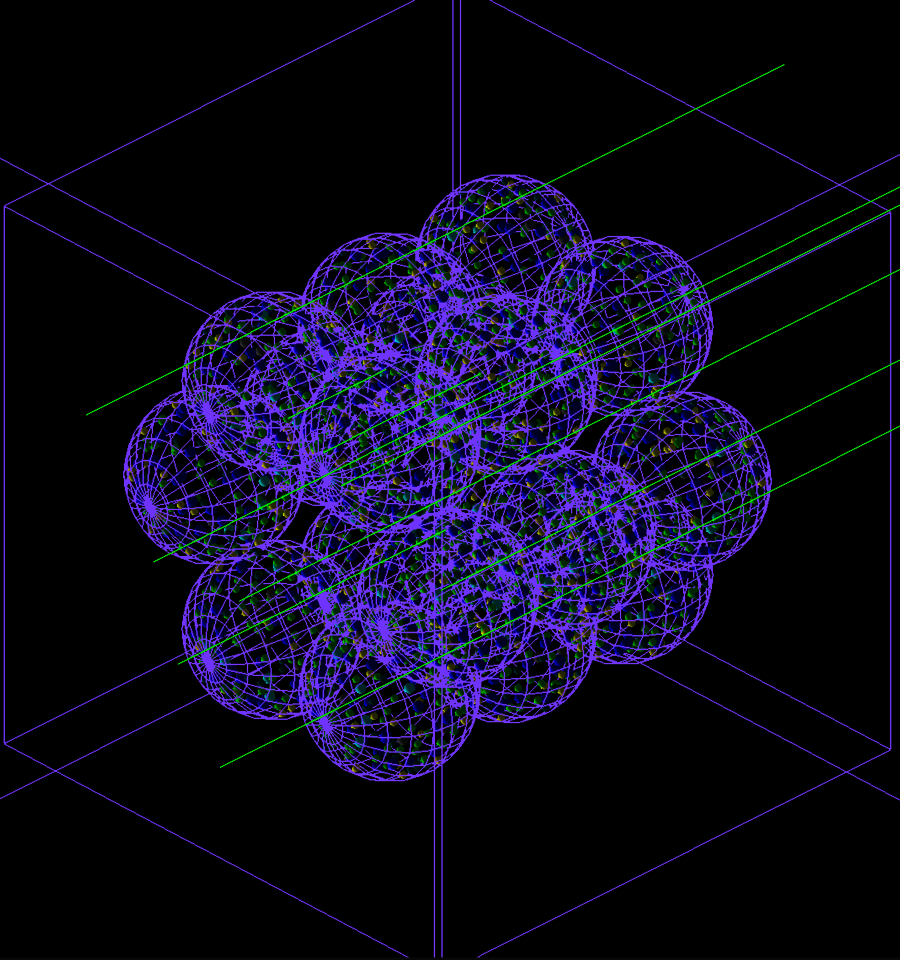

Ein innovatives Computermodell der menschlichen Lunge hilft Wissenschaftler*innen, erstmals zu simulieren, wie ein Strahlenstoß auf Zellebene auf das Organ einwirkt. Diese an der University of Surrey und am GSI Helmholtzzentrum für Schwerionenforschung in Darmstadt durchgeführten Forschungsarbeiten könnten zu gezielteren Krebsbehandlungen führen und die durch Strahlentherapie verursachten Schäden verringern.

Mehr als die Hälfte der Krebserkrankten erhält heute eine Strahlentherapie - doch eine zu hohe Dosis kann die Lunge schädigen. Dies kann zu Erkrankungen wie Pneumonitis und Fibrose führen. Um diese Verletzungen zu untersuchen, haben Forscher von GSI und der Universität Surrey mithilfe künstlicher Intelligenz ein neues Modell eines Teils der menschlichen Lunge entwickelt – Zelle für Zelle.

Professor Dr. Marco Durante, Leiter der Abteilung Biophysik bei GSI, sagte: "Mit BioDynaMo sind zum ersten Mal interaktive Modelle ganzer menschlicher Organe realisierbar. Damit können wir die Lungen einzelner Patient*innen auf eine Weise modellieren, die mit den sehr allgemeinen statistischen Methoden, die wir derzeit verwenden, einfach nicht möglich ist. Außerdem können wir damit untersuchen, wie Fibrose und andere Erkrankungen tatsächlich verursacht werden und wie sie sich im Laufe der Zeit entwickeln."